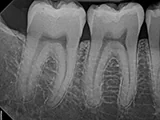

| X-Ray Example |

X-ray taken with the Pro Sensor |

Dental X-Ray Comparison

DentiMax

X-ray taken with the DentiMax sensorOpen Sensor